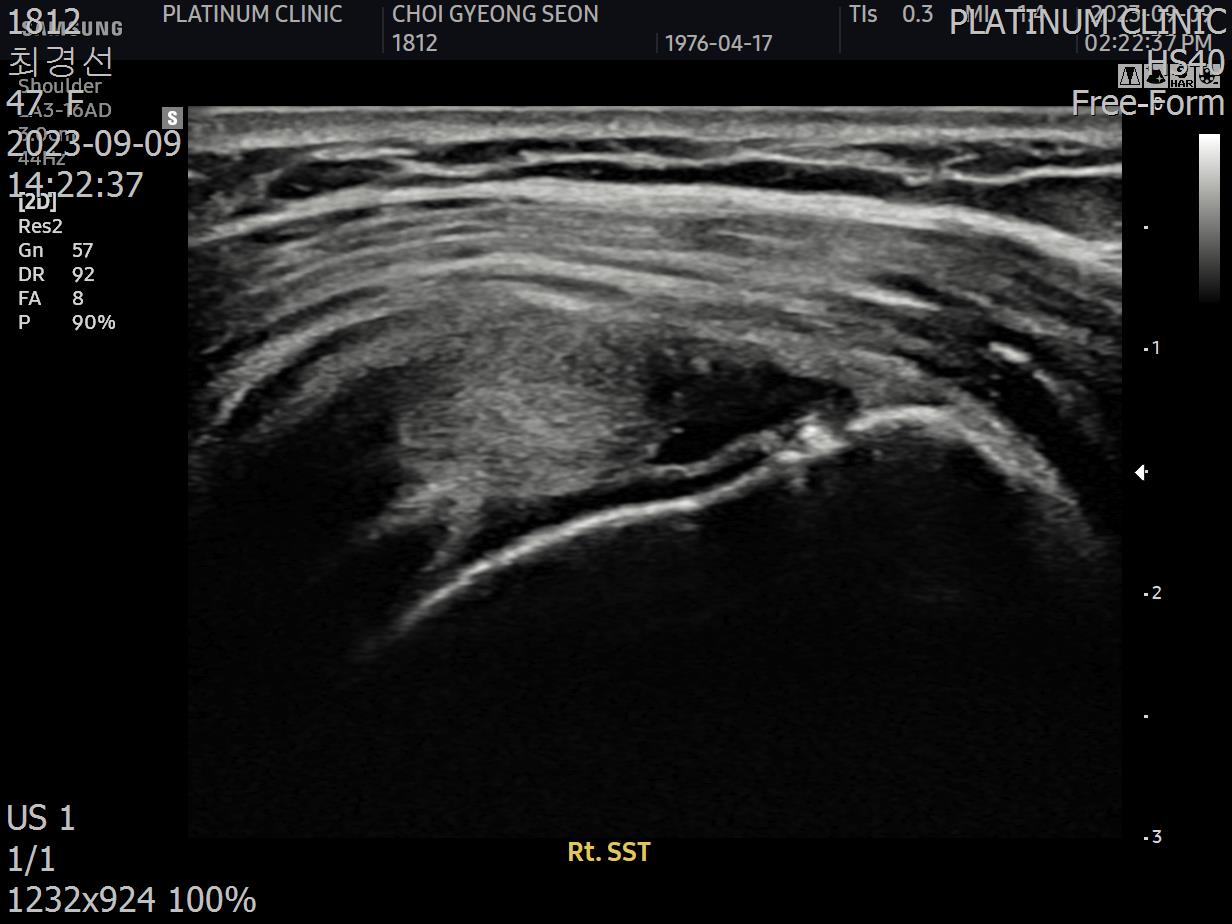

초음파 검사를 해보았습니다.

결과는 안타까웠습니다. 6개월 전보다 파열이 더 진행되어 있었습니다.

초음파 검사로 확인할 수 있습니다.

치료 전 초음파에서 검게 보이던 파열 부위가, 치료 후에는 정상 인대처럼 하얗게 보입니다. 이것이 구조적 회복의 증거입니다.

안 아파요"라는 주관적 느낌만으로 치료 완료를 판단하면 안 됩니다. 영상으로 확인된 구조적 회복이 있어야 진정한 치료입니다.

12주차: 초음파로 확인된 '재생'

마지막 주사로부터 6주 후, 팔로우업 검사를 진행했습니다.

초음파 결과:

이전에 검게 보이던 파열 부위가 하얗게 재생됨

인대 두께가 정상 범위로 회복됨

주변 염증 소견 소실